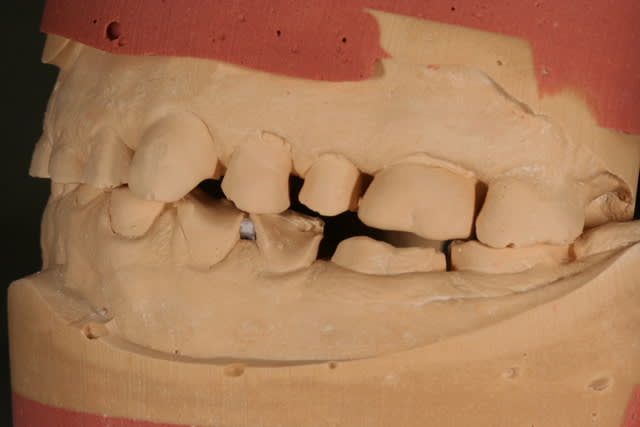

les modèles d'étude

on voit bien l'abrasion liée au bruxisme

l'érosion liée à l'acidité (une bière tous les soirs avant le repas, une pomme tous les soirs en dehors du repas)

l'usure des prémos liée a de mauvaises habitudes dans son métier (tournevis ou stylo au coin de la bouche)

Il ne me semble pas forcément nécessaire d'augmenter énormément la DV d'après les photos (peut être 2-3mm grand max?). Dans tous les cas, si le patient veut faire quelque chose qui dure dans le temps, je pense qu'il faut tout couronner.

S'il est motivé, je ferais montage directeur wax up en articu, puis provisoires solidarisées par secteurs en haut et en bas (de x7 à x5/x4, de x4 à x1 ou de x3 à x3). Tout faire le même jour est faisable et conseillé, même avec des clés c'est possible( par exemple en sectorisant les modèles un waxé, l'autre non. Avoir un bon prothésiste est primordial...) Dans ces cas là j'aime bien voir les patients porter leurs provisoires entre 6 mois et 1 an, en faisant des ajustements esthétiques et fonctionnels, et lorsqu'il y a des échecs cela permet de recadrer et de réajuster. Il est à mes yeux important de recréer des dents provisoires suffisamment cuspidées (sans forcément mettre des dents de jeune homme!) afin d'entrainer une modifications de ses mouvements musculaires de mastications, progressive et naturelle, ce qui aura également pour effet de diminuer sons bruxisme (utopiquement, de le supprimer, si la cause n'est que dentaire, ce qui n'est jamais vraiment le cas...)